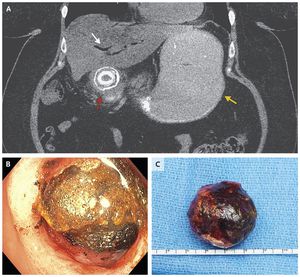

A 57-year-old woman presented to the emergency department with a 2-week history of nausea and vomiting. During the previous month, she had had intermittent episodes of right-upper-quadrant abdominal pain. Abdominal examination revealed a distended abdomen with decreased bowel sounds and mild epigastric tenderness without peritoneal signs. Computed tomography of the abdomen (Panel A) revealed pneumobilia (white arrow), gastric distention (yellow arrow), and a gallstone obstructing the proximal duodenum (red arrow). Bouveret’s syndrome is an uncommon form of gallstone ileus that is characterized by a gastric outlet obstruction caused by impaction of a gallstone in the pylorus or proximal duodenum after its passage through a cholecystoduodenal fistula. Patients with gallstone ileus may present with radiographic findings of Rigler’s triad (i.e., pneumobilia, small-bowel obstruction, and an ectopic gallstone). Mechanical lithotripsy with endoscopic removal of the stone was attempted in the patient (Panel B); however, the procedure was unsuccessful and was complicated by a perforation of the proximal duodenum. The patient then underwent an open laparotomy for repair of the duodenal perforation and removal of a mixed gallstone, which measured 4.4 cm in the greatest dimension (Panel C). She had complete resolution of symptoms and was discharged home 15 days after admission. Guilherme P. Ramos, M.D. Nian-En Chiang, M.D. Mayo Clinic, Rochester, MN source: nejm.org